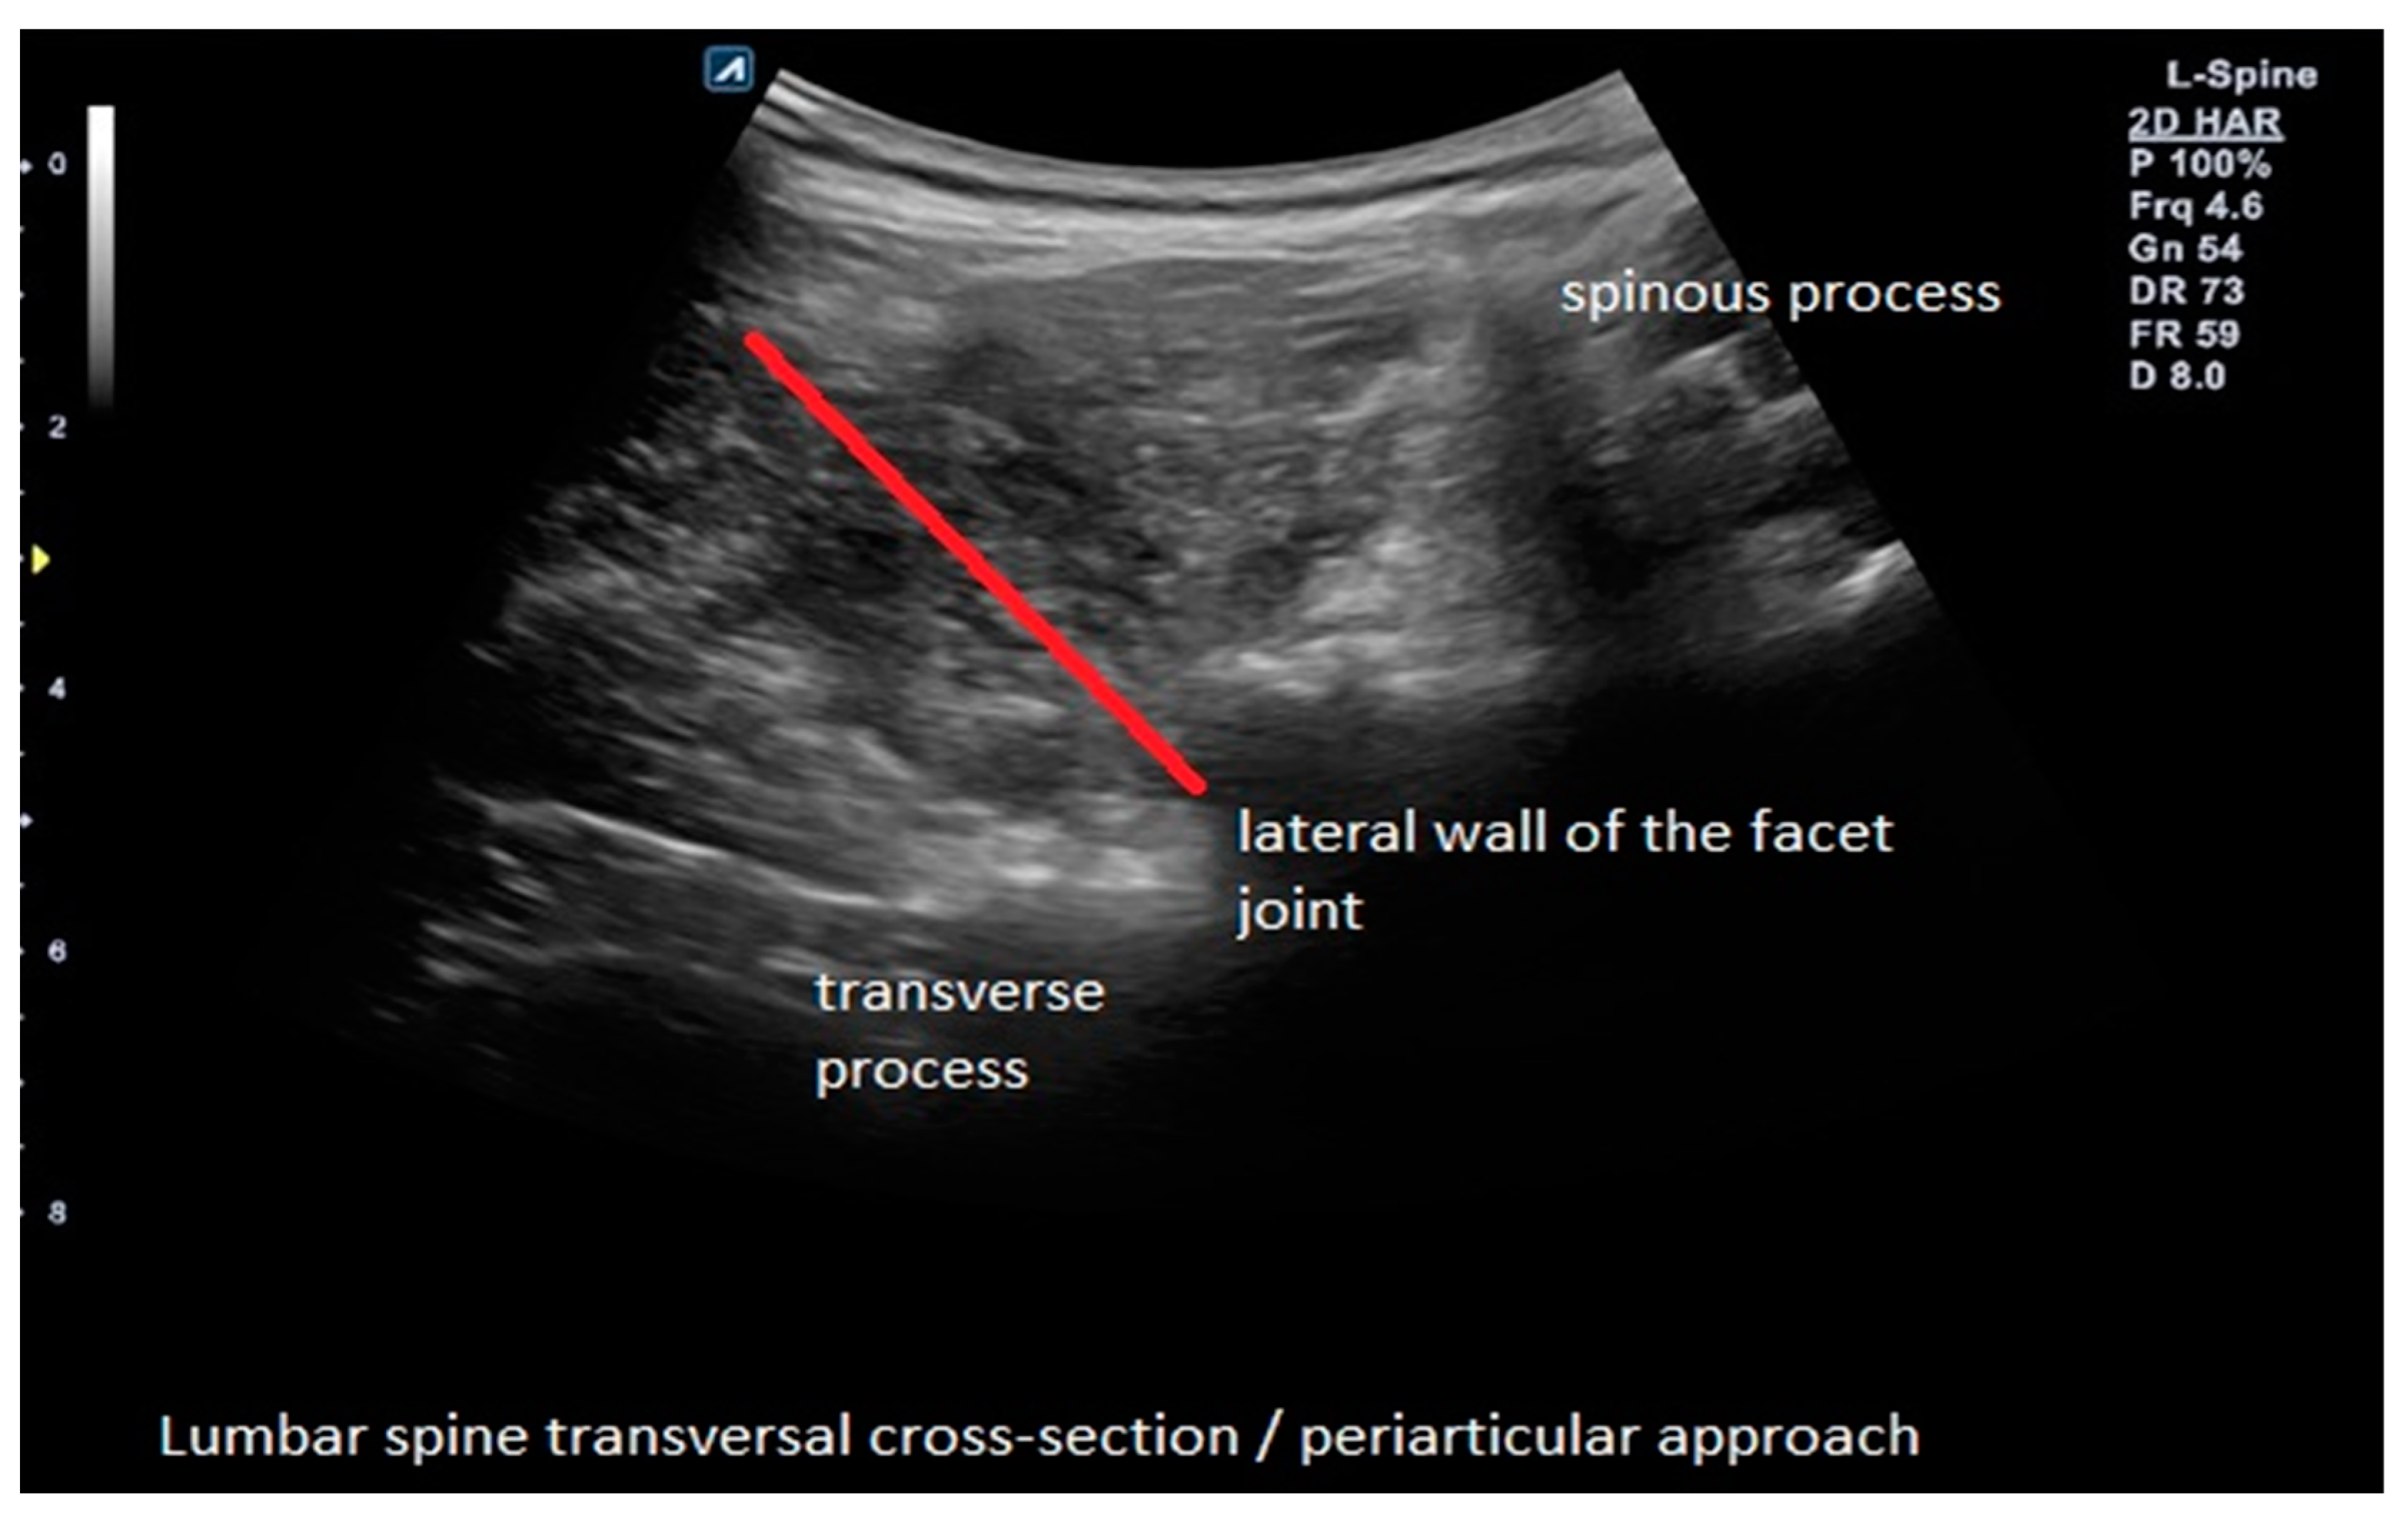

2.4. Interventions